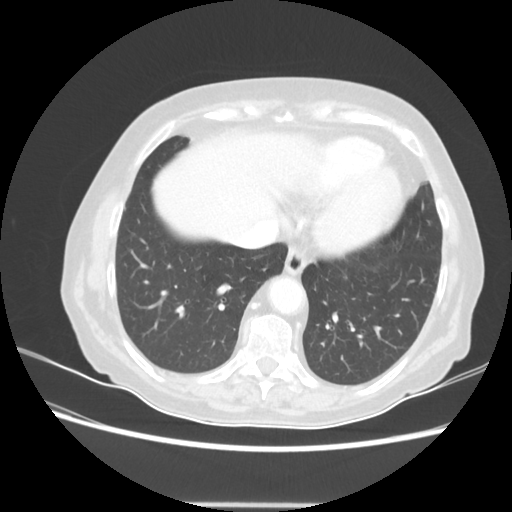

Targeted Slice 70 - Lung Window Analysis (Generated vs Real Venous)

0.654

Lung SSIM

173.9

Lung RMSE

69.6

Lung MAE

Average Lung Window Metrics Across All Slices (107 slices) - Generated vs Real Venous

0.678

Lung SSIM (Avg)

137.1

Lung RMSE (Avg)

56.3

Lung MAE (Avg)

Lung window (WL -600, WW 1500 β†’ Low βˆ’1350, High +150)

Original VENOUS CT scan

Generated VENOUS CT scan (A→B translation)